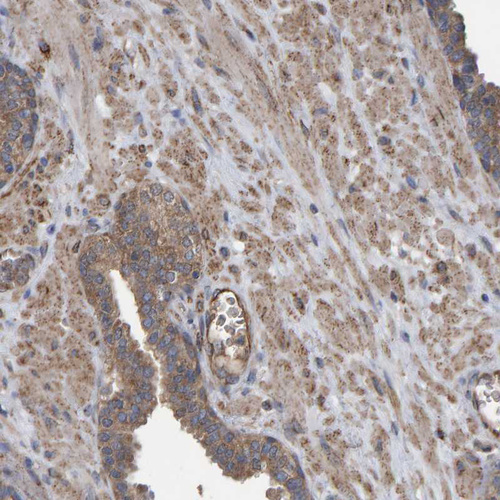

Immunohistochemical staining of human cerebral cortex shows strong positivity in neuropil.